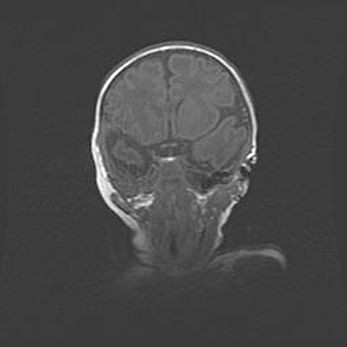

Мальформация Денди-Уокера. Киста задней черепной ямки.

Агенезия мозолистого тела.

Возраст: 2,5 месяца

Вес: 2420 г

Пол: женский

Окружность головы: 37 см

Срок гестации: 32 недели

Мальформация Денди—Уокера — редкий вид патологии ЦНС, представляющий собой врожденный порок развития каудального отдела ствола и червя мозжечка, ведущий к неполному раскрытию срединной (Мажанди) и латеральных (Лушка) апертур IV желудочка мозга. Для этогно синдрома характерна триада симптомов: гипотрофия червя мозжечка и/или полушарий мозжечка, кисты задней черепной ямки, гидроцефалия различной степени. В 70% случаев порок сочетается и с другими аномалиями головного мозга, в частности с агенезией мозолистого тела.